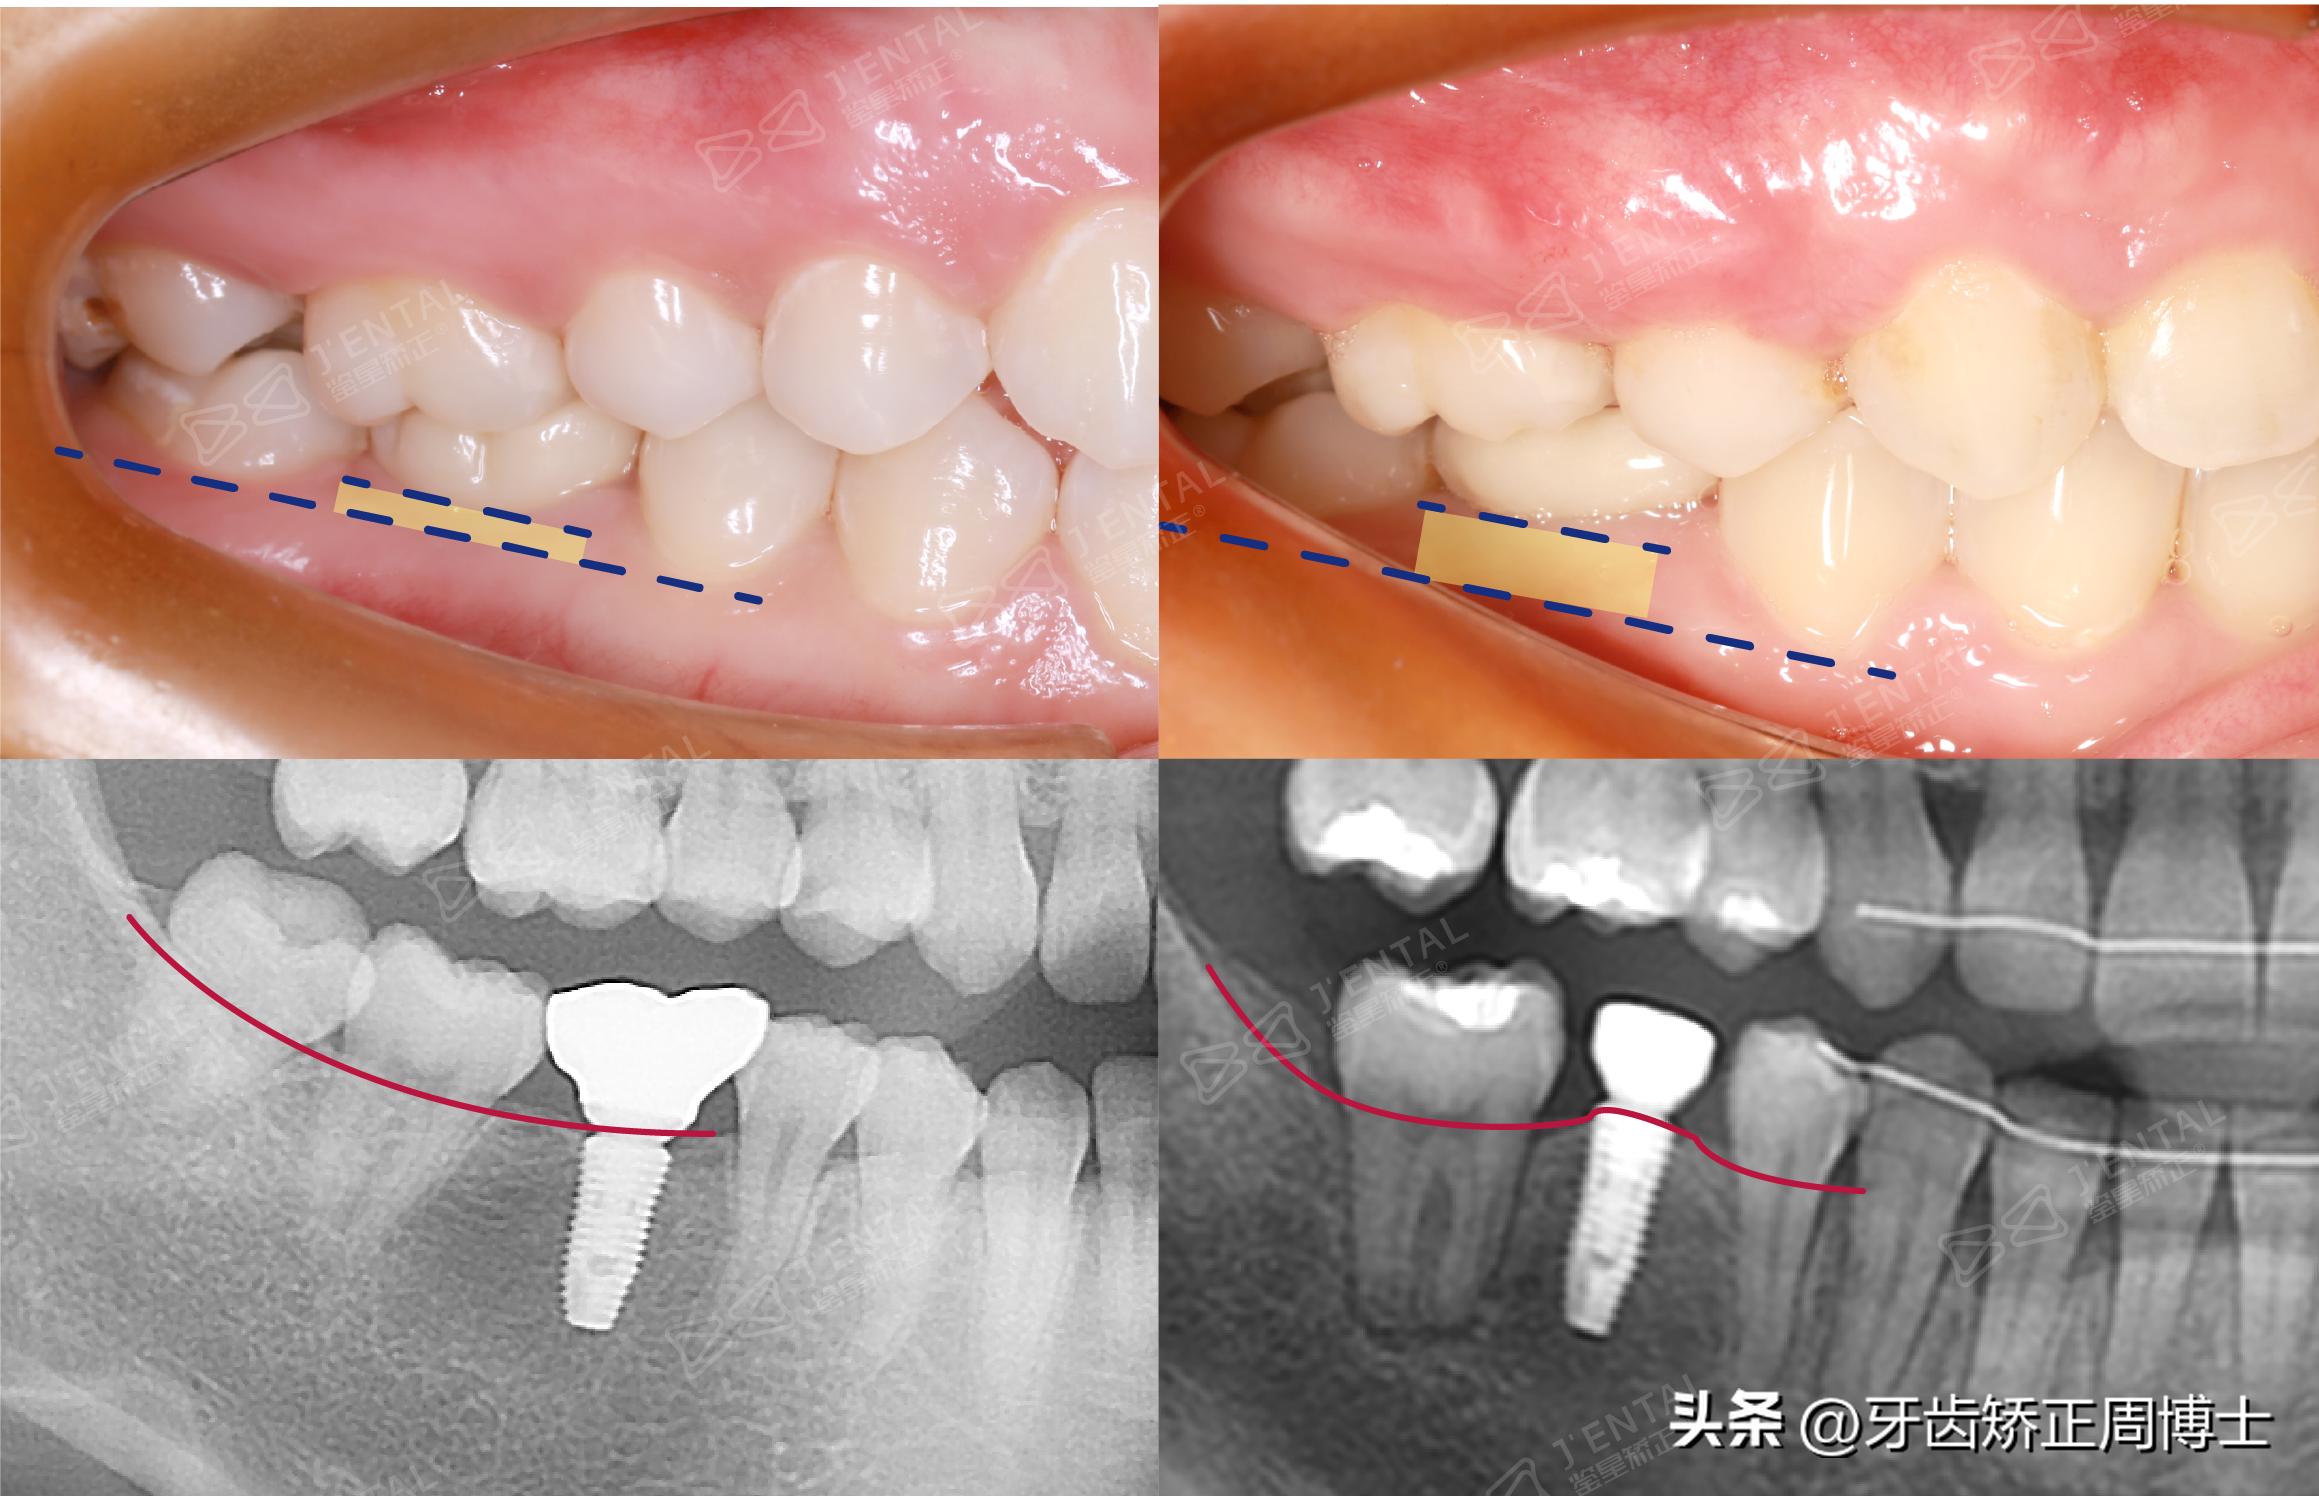

方案设计拔除上4下5,配合6颗骨钉做垂直向控制,做逆旋压低,在保留种植牙的情况下,去除上面的牙冠,把其他牙齿都压低好了,最终再重新做一个冠。

从下图看,正好因为这颗种植牙,通过种植牙和旁边牙齿的对比,所以反倒看出了压低牙齿的程度,我们是实实在在把牙齿压下去了。

种植体变成了后牙绝对压入的一把尺子